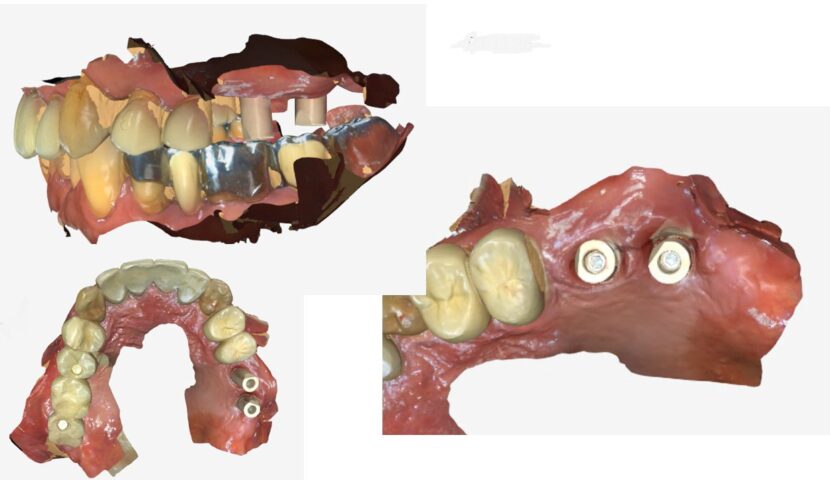

インプラント 症例1 症例2 症例3ガイドサージェリーについて 症例4歯牙移植 症例5 症例6 症例7 症例8